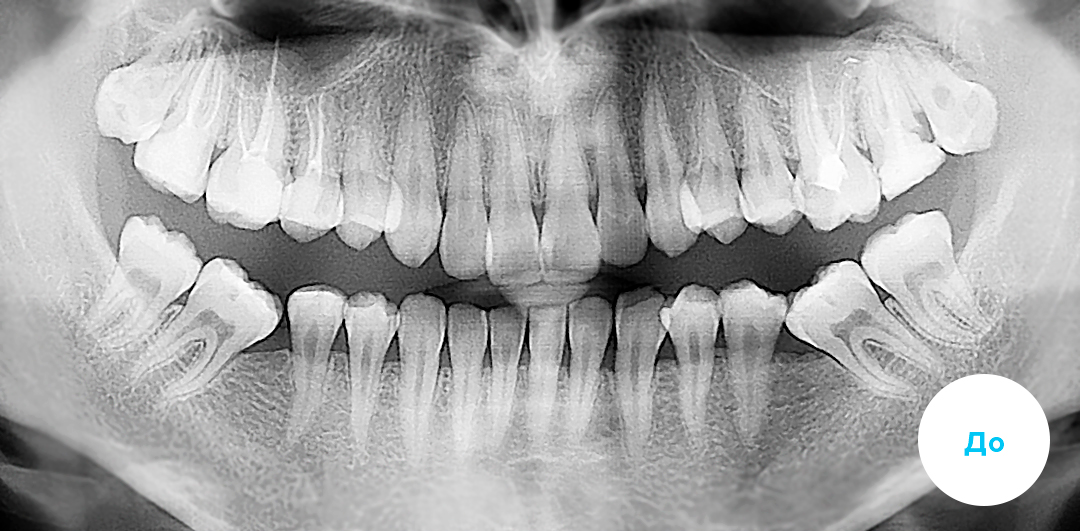

Индивидуальная брекет-система INSIGNIA (Инсигния) — это уникальная цифровая система от Ormco. Она моделируется при помощи CAD/CAM технологий на базе самолигирующих брекетов Damon. Эта опция возможна для двух разновидностей таких брекетов: керамических Damon Clear и металлических Damon Q. Изготавливаются индивидуально для каждого пациента по его “мерке” при этом, каждый брекет может быть как уникален, так и выбран из имеющейся серийной линейки. Компьютерное моделирование процесса ортодонтического лечения позволяет добиться прогнозированного и безукоризненно точного исправления прикуса и выравнивания зубов. Внешний вид системы INSIGNIA не отличается от обычных брекетов Damon – керамических или металлических, как и стоимость лечения на такой системе в клинике «Полный порядок».